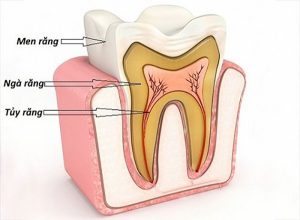

Giải phẫu răng: Khám phá cấu tạo và công dụng của răng

Một hàm răng chắc khỏe và sáng bóng là niềm ao ước của không ít người. Việc hiểu rõ về cấu tạo của răng cũng như cách chăm sóc thông qua những thông tin về giải phẫu răng bên dưới đây sẽ giúp bạn có thêm kiến thức cũng như phương pháp chăm sóc răng [...]